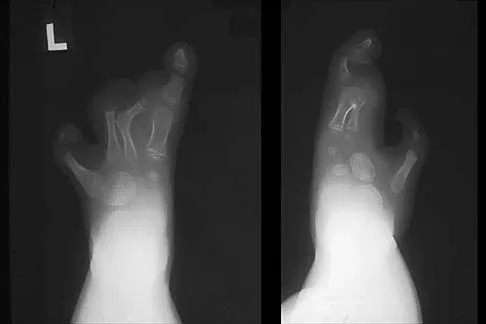

Fig. 37-33 Atlantoaxial rotatory fixation. A, Lateral radiograph shows wedge-shaped mass anterior to odontoid. B, Open-mouth odontoid view. C, CT scan. D, After C1-2 in situ fusion.